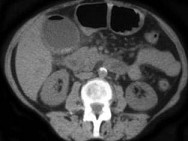

- 根据所提供的图像,该病例的最可能的诊断为